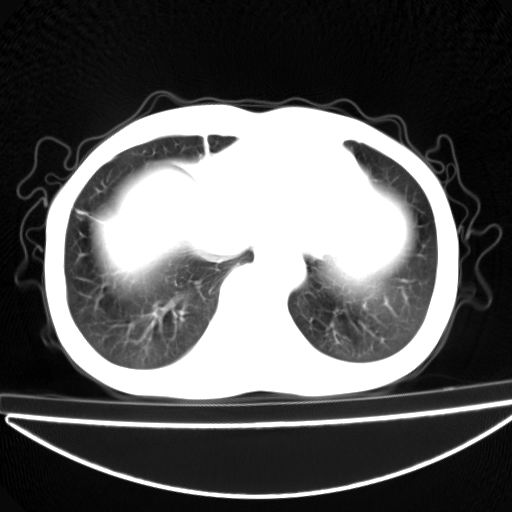

以下是引用杀毒软件在2009-4-28 17:58:00的发言:[br]考虑----左肺慢性肺脓肿形成继发上叶含气不良---抗炎后复查---待排肿瘤所致[br][br][本贴已被 杀毒软件 于 2009-4-28 18:01:26 修改过]